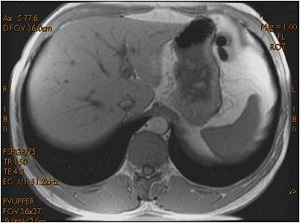

Gradient Echo Chemical Shift artifact

Chemical shift effects are seen when a voxel contains both fat and water and the TE is timed for the vectors to be in or out of phase.

Boundaries between fat and tissues with much water are either bright or dark. For some PSDs, such as FSPGR, the TE can be selected as In Phase or Out of Phase. When In Phase is selected, the fat/water border is bright and when Out of Phase is selected, the fat/water boundary is dark and structures can appear as if they have been outlined with a black marker.

To minimize the black border outline effect, select In Phase as the TE parameter, or manually enter a TE parameter as close to the fat/water in-phase time as possible.